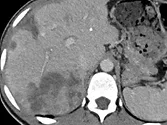

Figure 8. Carcinome hépatocellulaire. Sur l’examen initial (A, B), on observe

une lésion faiblement rehaussée au temps artériel (A), mais avec un lavage

évident au temps portal (B). Après six mois de chimiothérapie (C, D), la lésion est moins hypervascularisée au temps artériel (C), et de larges plages de nécrose sont apparues aux temps artériel et portal (D). La lésion est « PR » selon mRECIST